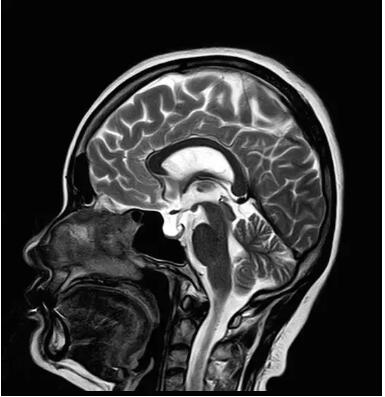

“螢火蟲”成像技術(shù) 顱內(nèi)腫瘤微小病灶檢出新發(fā)現(xiàn)

此技術(shù)主要用于神經(jīng)系統(tǒng)惡性腫瘤,以及其他腫瘤腦轉(zhuǎn)移瘤篩查。傳統(tǒng)情況下做腫瘤腦轉(zhuǎn)移篩查,很容易漏掉5mm以下小病灶,臨床發(fā)現(xiàn)后干預(yù)治療比較晚,要實現(xiàn)2mm高空間分辨率和超薄層全腦掃描在保證信噪比的情況下需要很長時間大概十多分鐘,而且薄層增強序列顱內(nèi)血管呈高亮信號,會干擾顱內(nèi)小病灶的觀察,血管和小病灶區(qū)分困難。佳能”螢火蟲”成像技術(shù)既可以實現(xiàn)高空間分辨率和超薄層(最薄可實現(xiàn)0.2mm)全腦掃描,掃描時間短,2-3分鐘即可實現(xiàn)全腦3D掃描,同時避免了血管高亮信號的干擾,對顱內(nèi)原發(fā)或繼發(fā)的微小腫瘤檢查有重大意義。“螢火蟲”成像技術(shù)具有磁敏感效應(yīng),對于亞急性血敏感敏感,可以區(qū)分出血和強化的腫瘤。